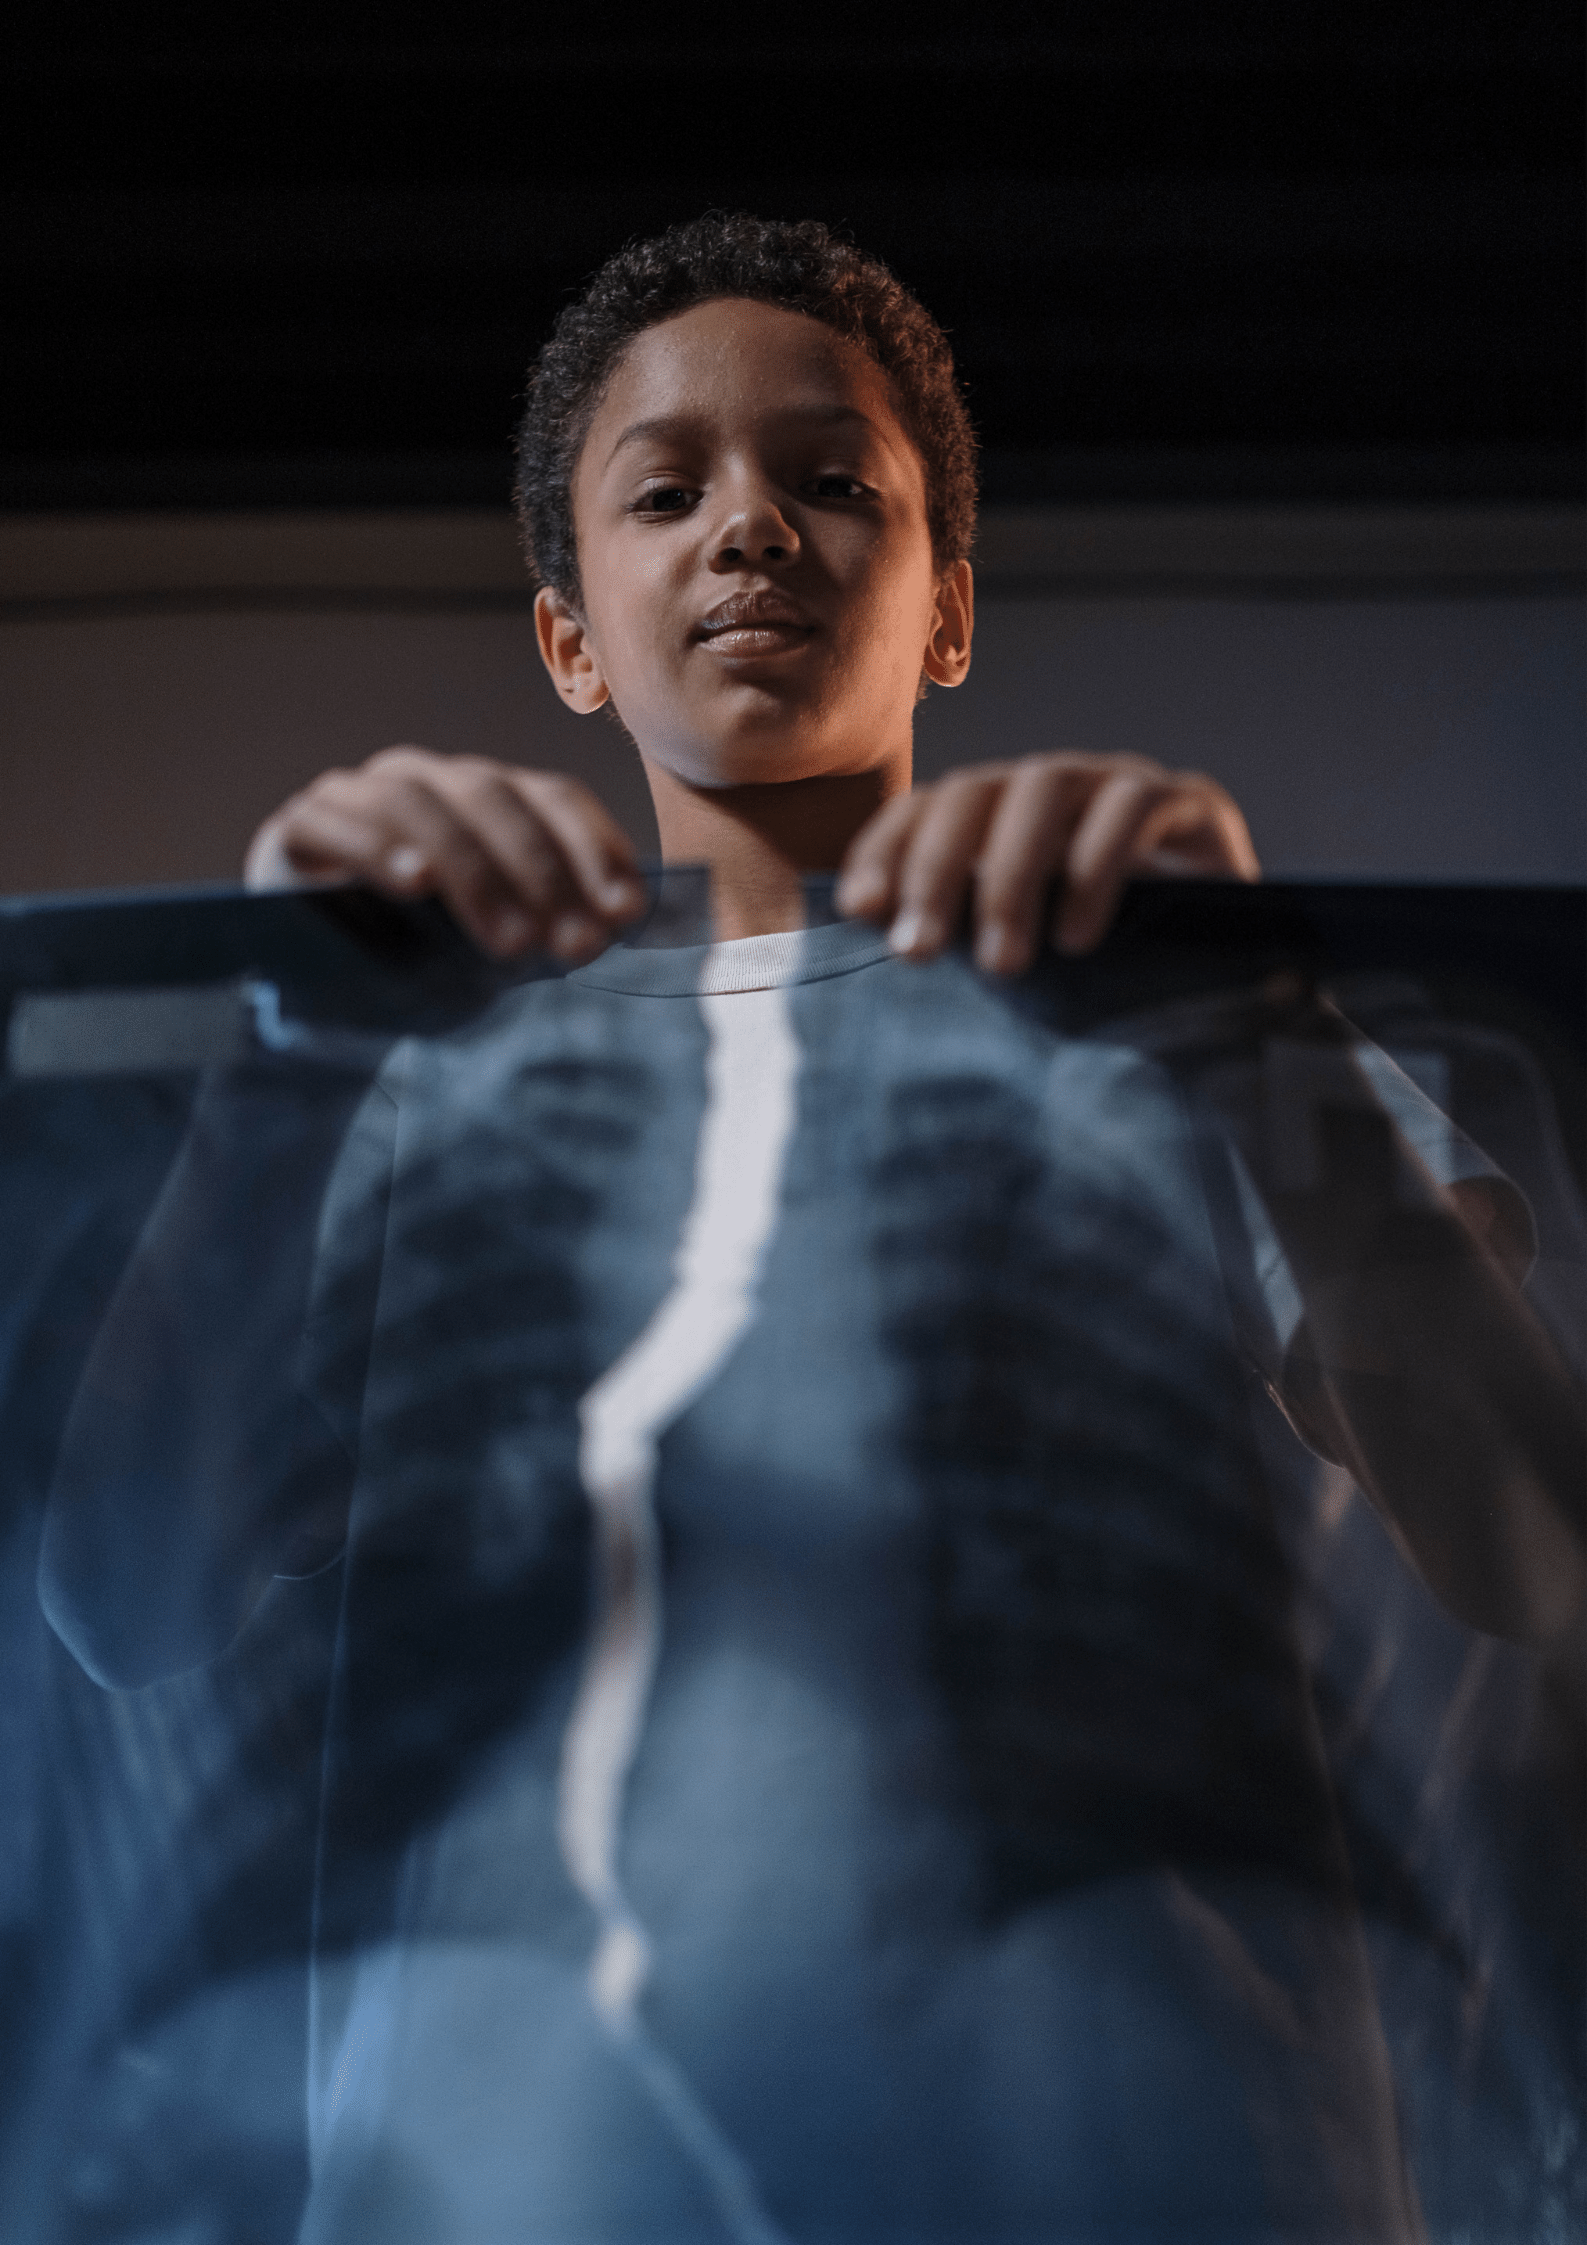

Our branch of medicine that uses imaging technology to diagnose and treat diseases. Doctors who specialize in radiology are called Radiologists.

A variety of imaging techniques are used to diagnose or treat diseases. Radiology is divided into two different areas, Diagnostic Radiology and Interventional Radiology .

Diagnostic Radiology (DR) refers to the field of medicine that uses non-invasive imaging scans to diagnose a patient. The tests and equipment used sometimes involves low doses of radiation to create highly detailed images of an area.